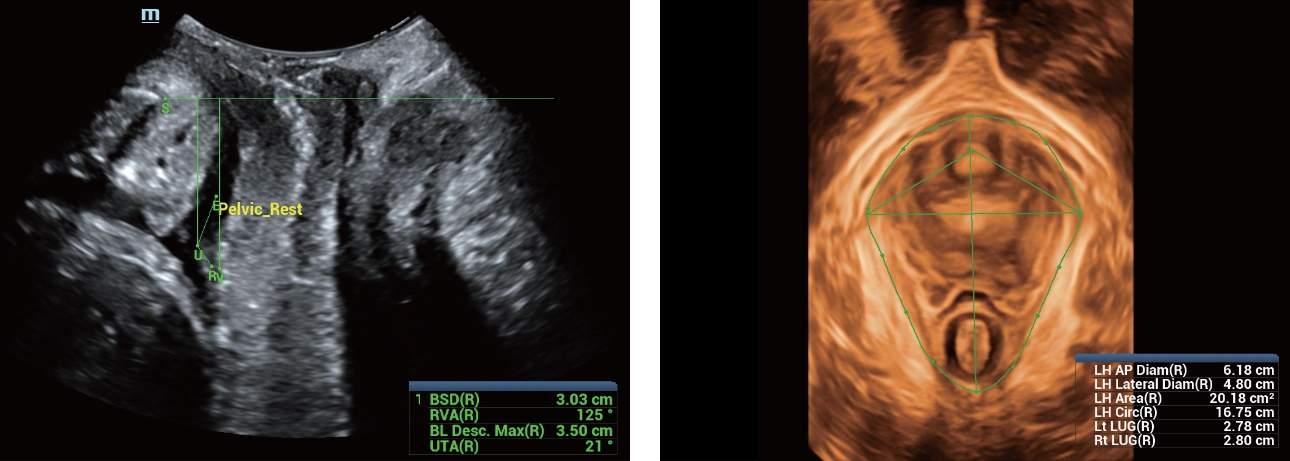

С момента основания компания Mindray непрерывно ищет новые способы повышения точности диагностики. Основанная на самой передовой технологии ZONE Sonography? новая платформа ZST+, выводит качество ультразвуковой визуализации системы Resona 7 на более высокий уровень за счет использования зонного сканирования и канальной обработки данных.

Обеспечивая качество изображения уровня премиум, Resona 7 также повышает клинические возможности исследования при помощи революционной системы V Flow, предназначенной для оценки гемодинамических показателей сосудов; обеспечивает интеллектуальное получение из 3D данных наиболее важных проекций для диагностики ЦНС плода. Сочетая в себе интуитивно понятное сенсорное управление с распознаванием жестов и все важные клинические характеристики, передовая система Resona 7 настоящая новая волна в сфере ультразвуковых инноваций.Благодаря перечисленным выше характеристикам, Resona 7 является доступным решением премиум-класса, которое удовлетворяет высоким требованиям клинической точности и эффективной диагностики в условиях современной перегруженной больничной среды.